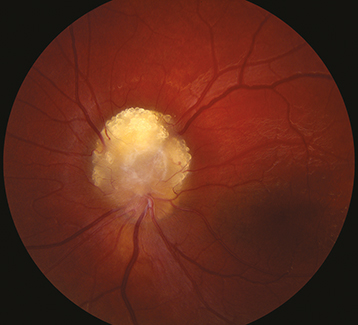

Figure 13.11.6: Retinal capillary hemangioma/hemangioblastoma.

Rapuano9781975243722-ch013_f010.jpg

Retinal capillary hemangioma/hemangioblastoma (small, round, orange–red tumor with a prominent dilated feeding artery and draining vein), sometimes associated with subretinal exudates, subretinal fluid, and total retinal detachment. Bilateral in 50%. Can produce macular traction and epiretinal membrane. Peripheral lesions often present with macular exudates.